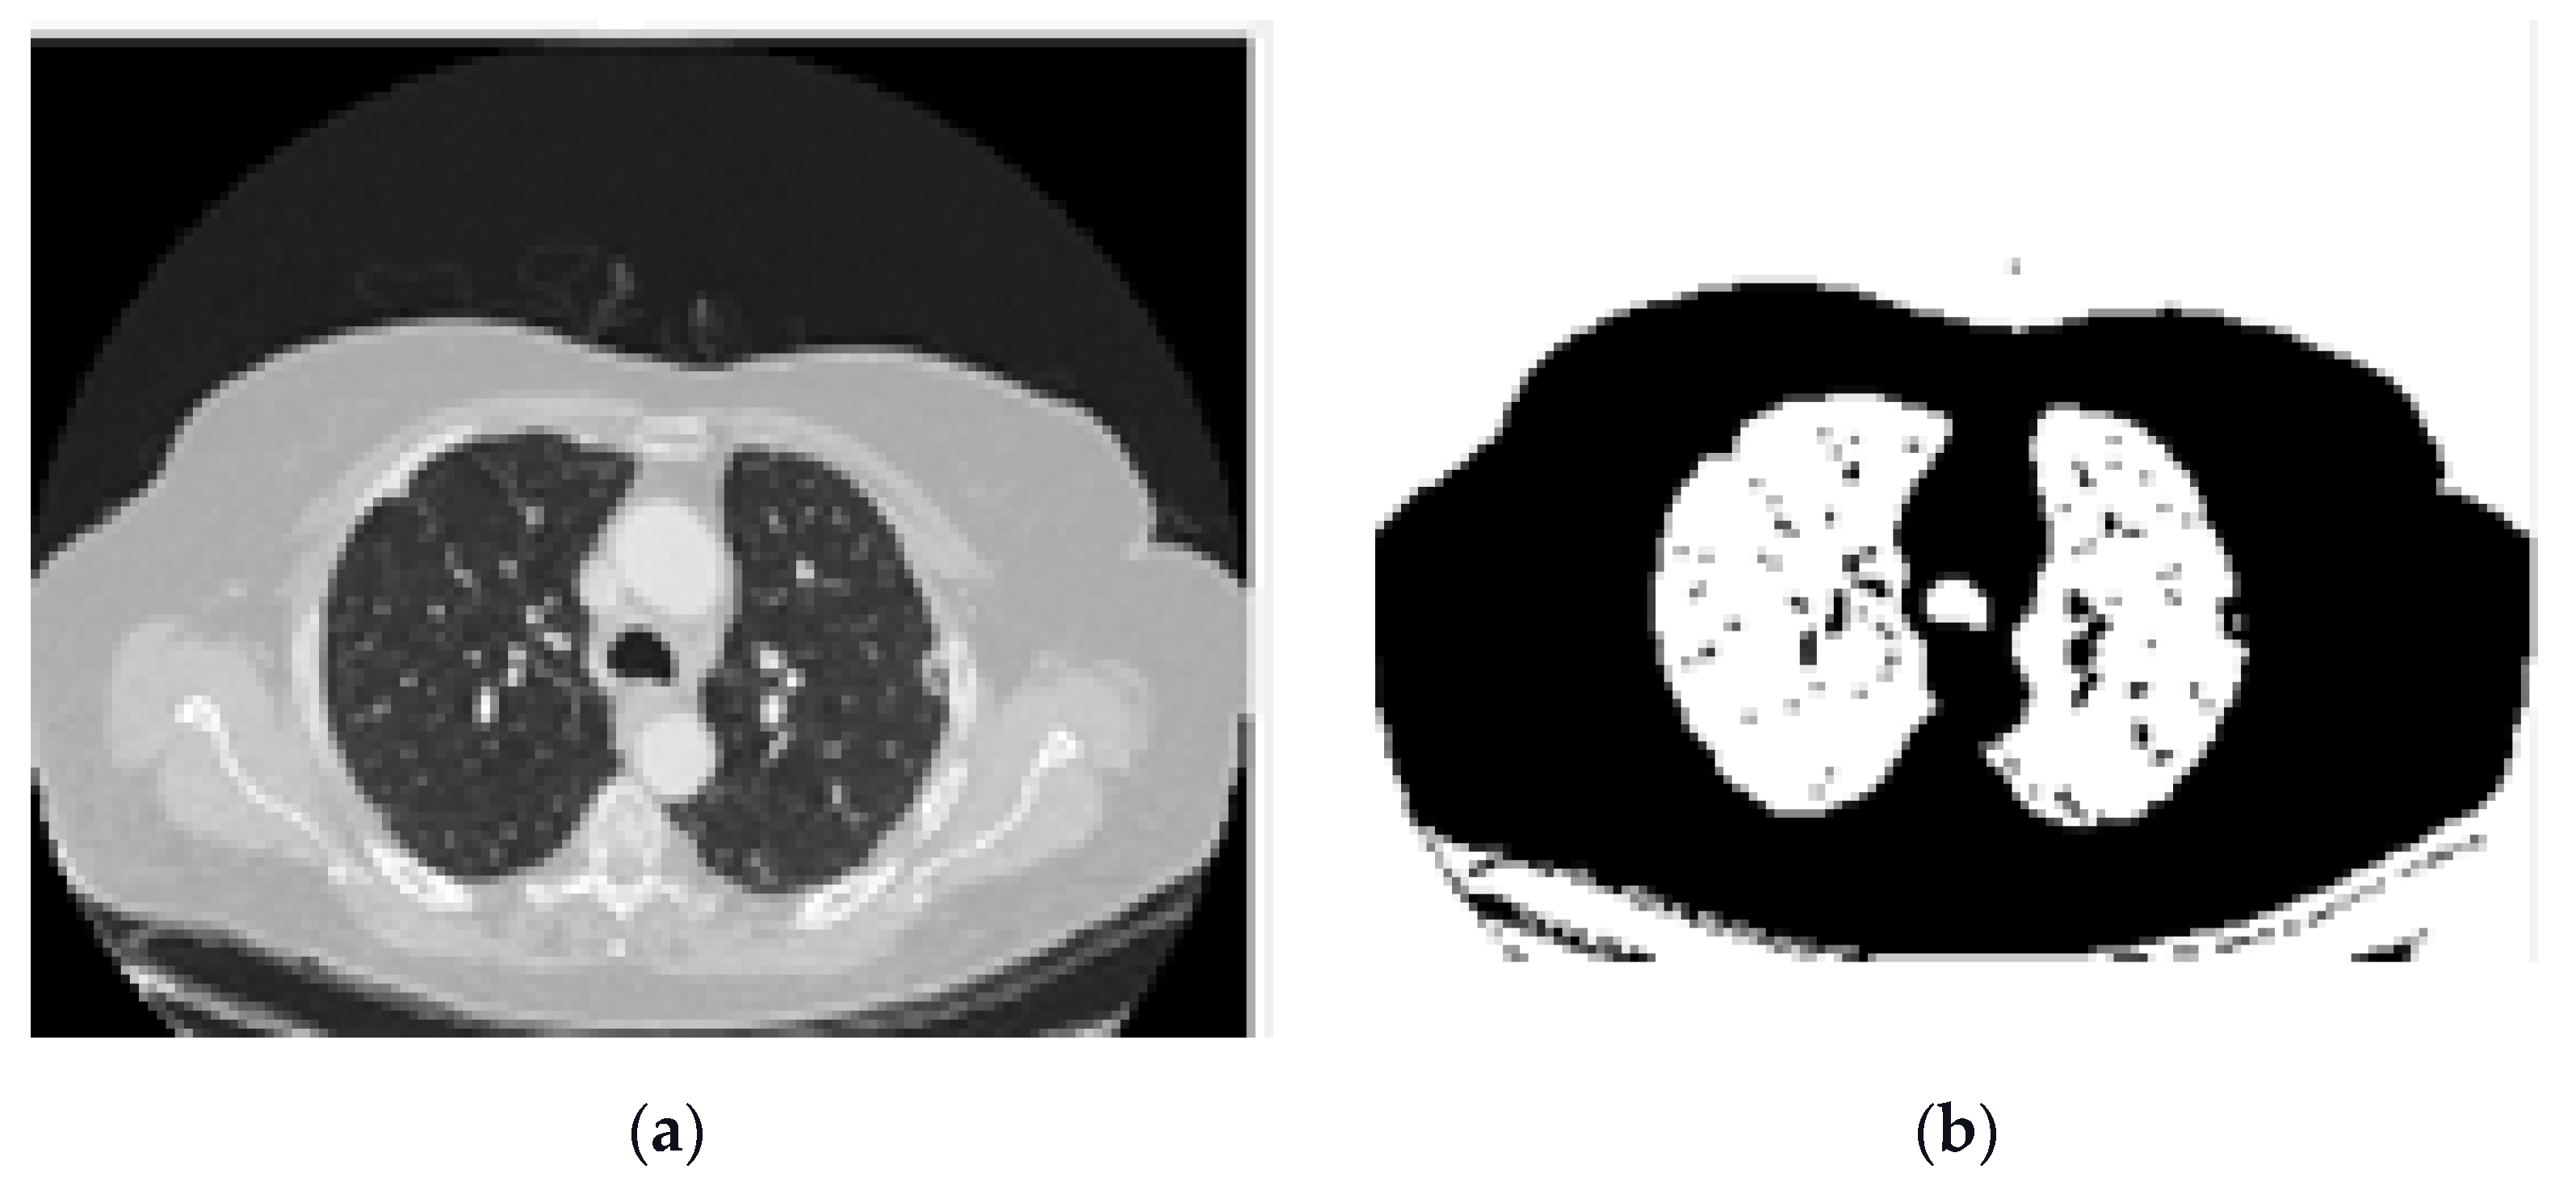

- Labelling the image: Pixel neighbourhoods with the same intensity level can consider being a connected region. When this process is applied to the entire image some connected regions are formed. Figure 4a shows connected regions of integer array of the images that are labelled.

- Removing the blobs connected to the CT image border: To classify the images correctly, the regions connected to the image border are removed, as shown in Figure 4c.